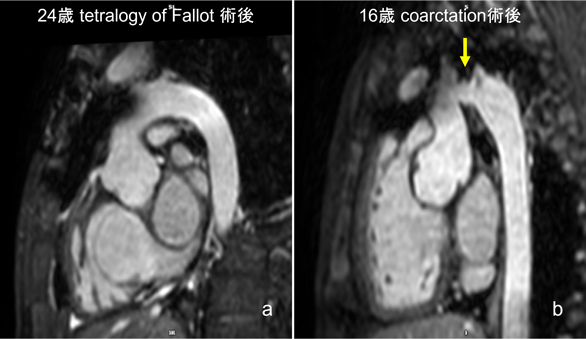

心室だけでなく,aortaなどの大血管形態評価も可能である(Fig. 6).

Fig. 6 Left: Normal arch (anterior aortic artifact). Right: Aortic coarctation (yellow arrow).